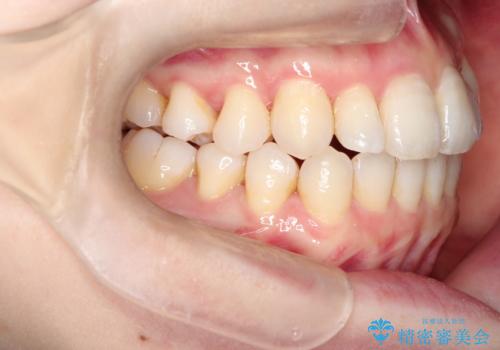

インビザラインで八重歯の矯正

- 八重歯を治したいとのことで、来院されました。

インビザラインにて、上顎の歯と歯の間をわずかに削り、並べる計画としました。

使用時間を守っていただけたので、比較的スムーズに矯正を終了することができました。